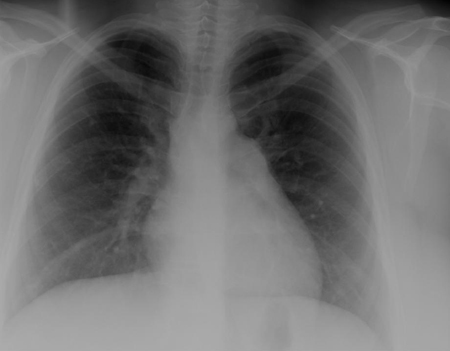

CXR and ECG can be normal in small VSDs. In larger defects, there is cardiac enlargement and increased pulmonary vascular markings on CXR, and ECG reveals left ventricle hypertrophy; right ventricle hypertrophy can occur with larger defects. Inlet-type VSDs are associated with left axis deviation on ECG. Echocardiography provides important information regarding the anatomy of the defect, the volume of the shunt, and right ventricular pressure.[25][26][Figure caption and citation for the preceding image starts]: CXR demonstrating pulmonary overcirculationMayo Clinic Foundation [Citation ends].